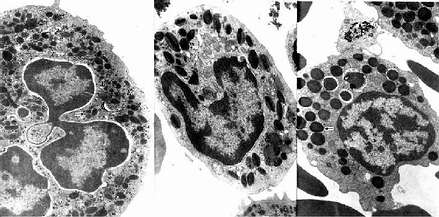

图5-5 人三种粒电镜像 ×17800

左图:中性粒细胞(白求恩医科大学尹昕、朱秀雄教授供图)

中图:嗜酸性粒细胞 左图:嗜碱性粒细胞

↑特殊颗粒,(

嗜天青颗粒 )嗜天青颗粒

中性粒细胞的胞质染成粉红色,含有许多细小的淡紫色及淡红色颗粒,颗粒可分为嗜天青颗粒和特殊颗粒两种。嗜天青颗粒较少,呈紫色,约占颗粒总数的20%,光镜下着色略深,体积较大;电镜下呈圆形或椭圆形,直径0.6~0.7μm,电子密度较高(图5-4,5-5),它是一种溶酶体,含有酸性磷酸酶过氧化物酶等,能消化分解吞噬的异物。特殊颗粒数量多,淡红色,约占颗粒总数的80%,颗粒较小,直径0.3~0.4μm,呈哑铃形或椭圆形,内含碱性磷酸酶吞噬素溶菌酶等。吞噬素具有杀菌作用,溶菌酶能溶解细菌表面的糖蛋白

2.嗜酸性粒细胞 嗜酸性粒细胞(eosinophilicgranulocyte,eosinophil)占白细胞总数的0.5%-3%。细胞呈球形,直径10~15μm,核常为2叶,胞质内充满粗大(直径0.5~1.0μm)、均匀、略带折光性的嗜酸性颗粒,染成桔红色(图5-2)。电镜下,颗粒多呈椭圆形,有膜包被,内含颗粒状基质和方形或长方形晶体(图5-4,5-5)。颗粒含有酸性磷酸酶、芳基硫酸酯酶、过氧化物酶和组胺酶等,因此它也是一种溶酶体。

3.嗜碱性粒细胞 嗜碱性粒细胞(basoophilic granulocyte,basophil)数量最少,占白细胞总数的0~15。细胞呈球形,直径10-12μm。胞核分叶或呈S形或不规则形,着色较浅。胞质内含有嗜碱性颗粒,大小不等,分布不均,染成蓝紫色,可覆盖在核上(图5-2)。颗粒具有异染性甲苯胺蓝染色呈紫红色。电镜下,嗜碱性颗粒内充满细小微粒,呈均匀状或螺纹状分布(图5-4,5-5)。颗粒内含有肝素和组胺,可被快速释放;而白三烯则存在于细胞基质内,它的释放较前者缓慢。肝素具有抗凝血作用,,组胺和白三烯参与过敏反应。嗜碱性粒细胞在组织中可存活12-15天。